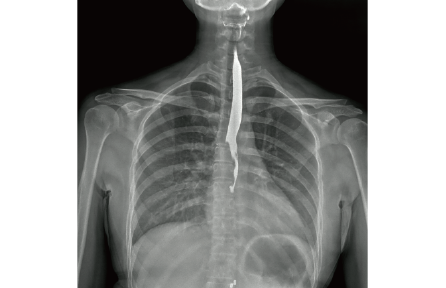

l 数字化透视

适用于身体各部位透视功能(如胸部、腹部等)

l 数字化造影

可以进行对比研究,例如食管造影、静脉肾盂造影和输卵管造影